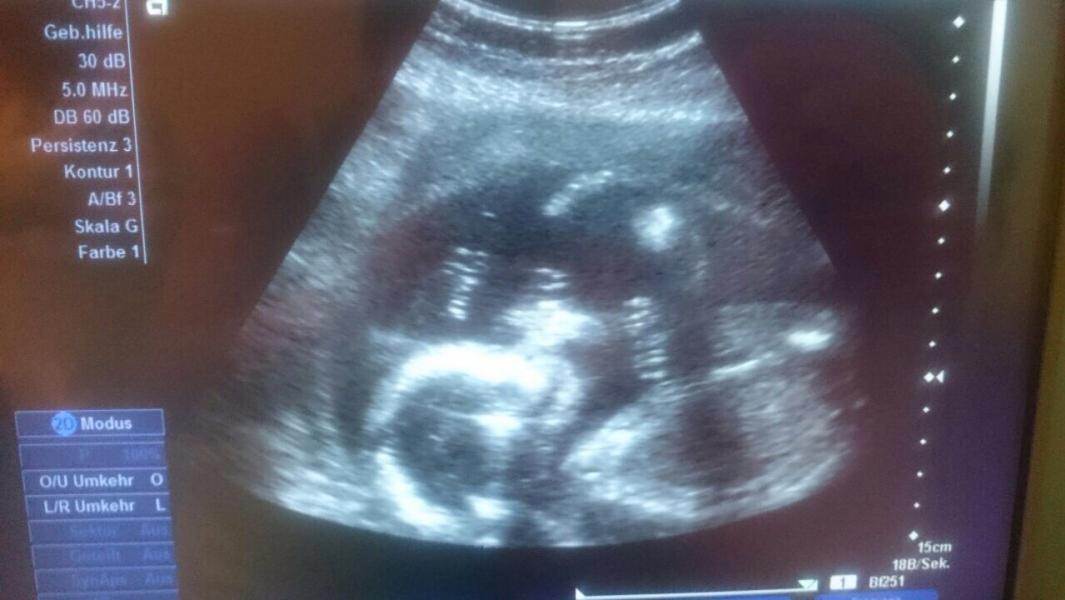

П.с. На фото моему шилопопу ровно 20 недель. Было 20 мая и я узнала, что мы ждём Даниила 💛